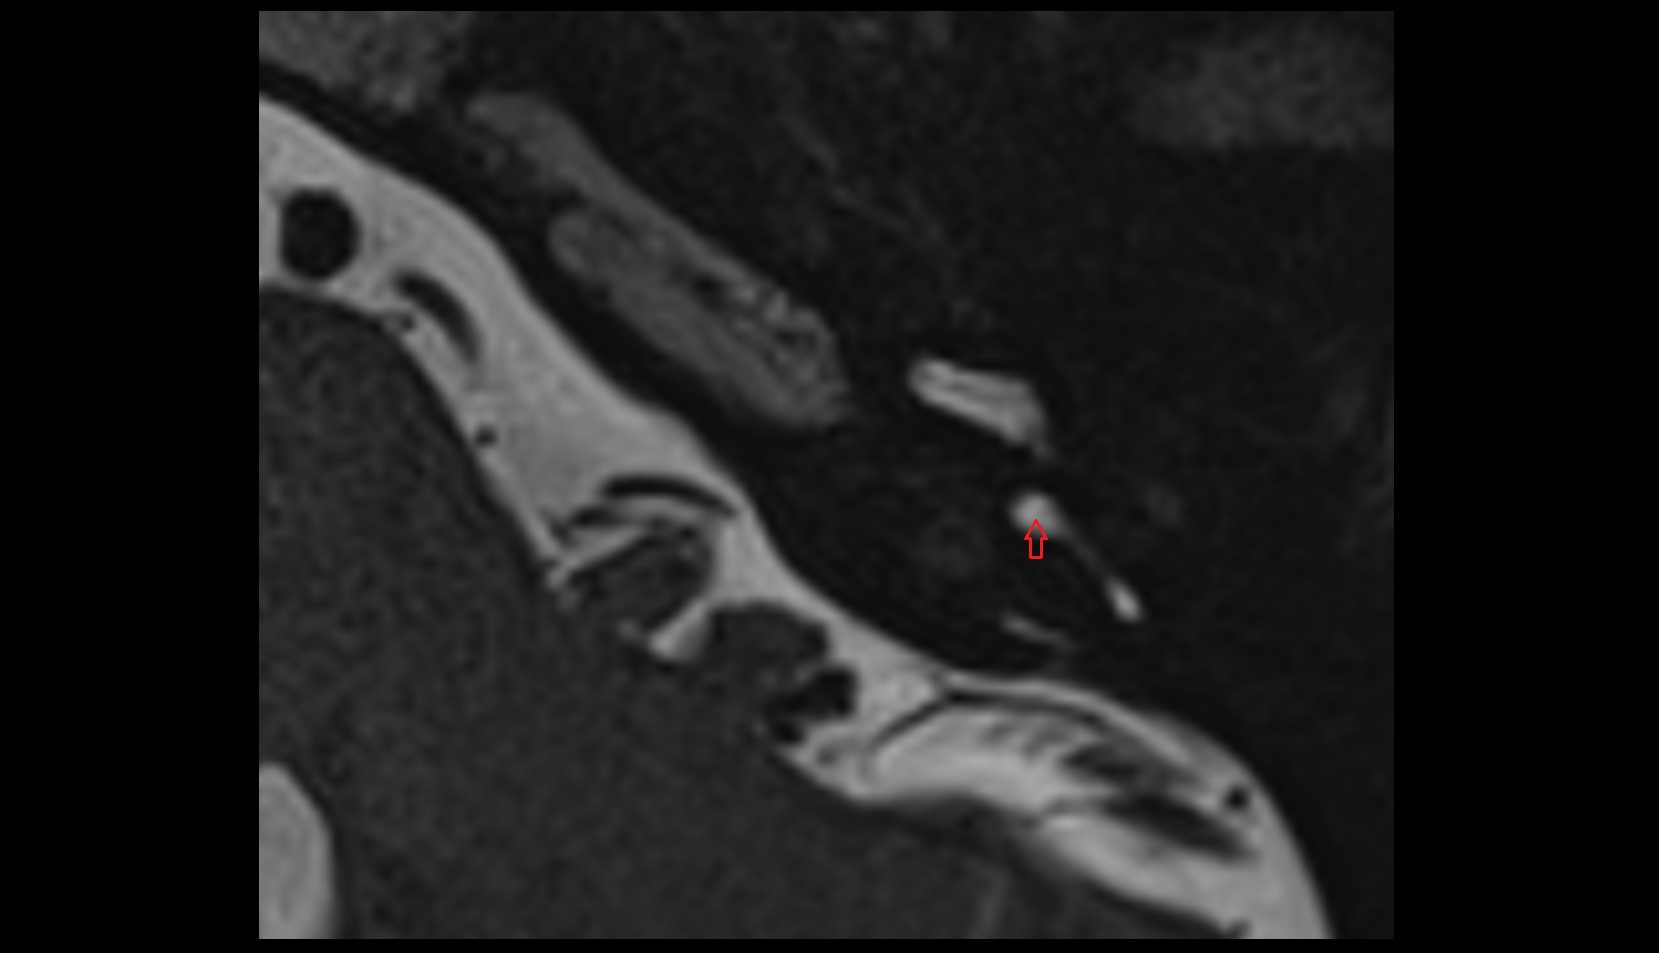

- Temporomandibular joint

- Articular disc of temporomandibular joint

- Articular eminence

- Mandibular condyle

- Mandibular fossa